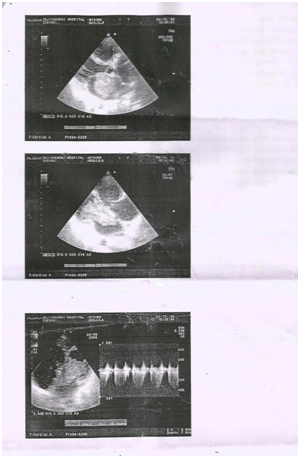

64 year old female who presented with dyspnea for two months duration was evaluated in our department. Echocardiogram showed a cauliflower like mass with multiple protruding villous appearance attached to the inter atrial septum near the foramen ovale suggestive of left atrial myxoma traversing the mitral valve orifice causing mitral valve obstruction. Patient was referral to cardiothoracic surgeon for surgical excision.

We present a 64_ year old female who presented with symptoms of dyspnea NYHA class III, and palpitations for two months duration. Clinical examination revealed pallor, and a mid diastolic murmur in mitral area. ECG was within normal limits. Echocardiogram showed a cauliflower like mass with multiple protruding villous appearance attached to the inter atrial septum near the foramen ovale traversing the mitral valve orifice causing mitral valve obstruction. Patient was referred to cardiothoracic surgeon for surgical excision (Figure 1 & 2).

Figure 2Clinical examination 2..